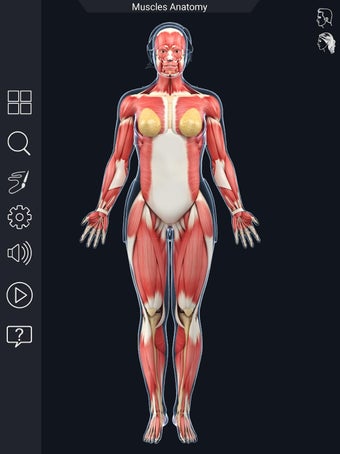

Den mest omfattande mobilappen som finns i världen för att studera muskelanatomi, som låter dig rotera 360°, zooma och flytta kameran runt en mycket realistisk 3D-modell.

Det finns mycket detaljer tillgängliga för varje muskel, vilket gör det till ett utmärkt verktyg för medicinstudenter.

Det finns många verktyg tillgängliga för varje muskel, inklusive: